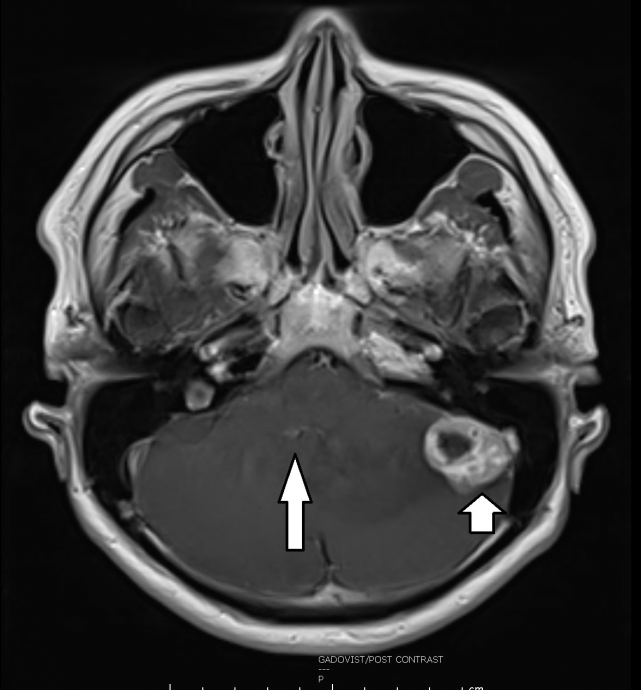

看了耳鼻喉专科,医生告知耳鼻喉一切正常,但脑部扫描影像却让人无法乐观,因为医生在文先生的左小脑下端发现一颗肿瘤。

才刚过完年,文太太就扶着先生出现在我的诊所。从脑部扫描影像所见,文先生左小脑下端的肿瘤约有3~4公分大,推挤着小脑排水道,导致积水,并压迫左边颜面和左耳听觉神经线,造成耳鸣、头痛、步态不稳、反应迟缓等症状。

化验报告出炉,长在文先生小脑内的这颗肿瘤是小脑血管细胞瘤(Haemangioblastoma),虽是良性肿瘤,但由于10%的小脑血管细胞瘤病人患有Von hippel-lindau综合症(简称VHL),所以我建议文先生必须做全身健康检查,以便排除这10%的可能性。